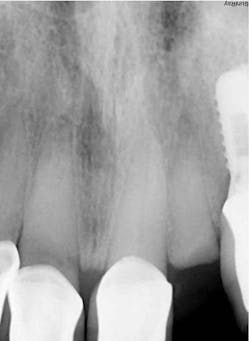

The decision to use the Ditron Implant System was based on the following treatment plan: extraction and immediate implant placement, with immediate provisionalization using a final titanium abutment. Extraction and immediate implant placement with immediate provisionalization have shown to be quite successful.

Maintaining initial stability is important when an implant is placed in a compromised extraction site, since there is less bone-to-implant contact there than in a healed site. Because of its architecture, the Ditron Ultimate implant offers a very high initial stability and strong abutment connection. The implant profile uniformly distributes the stress directly to the bone, which results in a more even distribution of force and lower long-term crestal resorption. This implant system has a good aggressive thread profile and a secure abutment connection, which are both key characteristics. The microthreads on the implant’s reverse conical neck (RCN) greatly increase the implant’s ability to resist axial displacement, and the mechanical stimulus the microthreads provide helps to preserve the peri-implant marginal bone. By inserting an Ultimate implant, 5.57 mm3 of bone will be saved compared to that of a non-RCN implant.7

First visit: Extraction and immediate implant placement, immediate placement of the final abutment prepared intraorally, and then a provisional out of function.